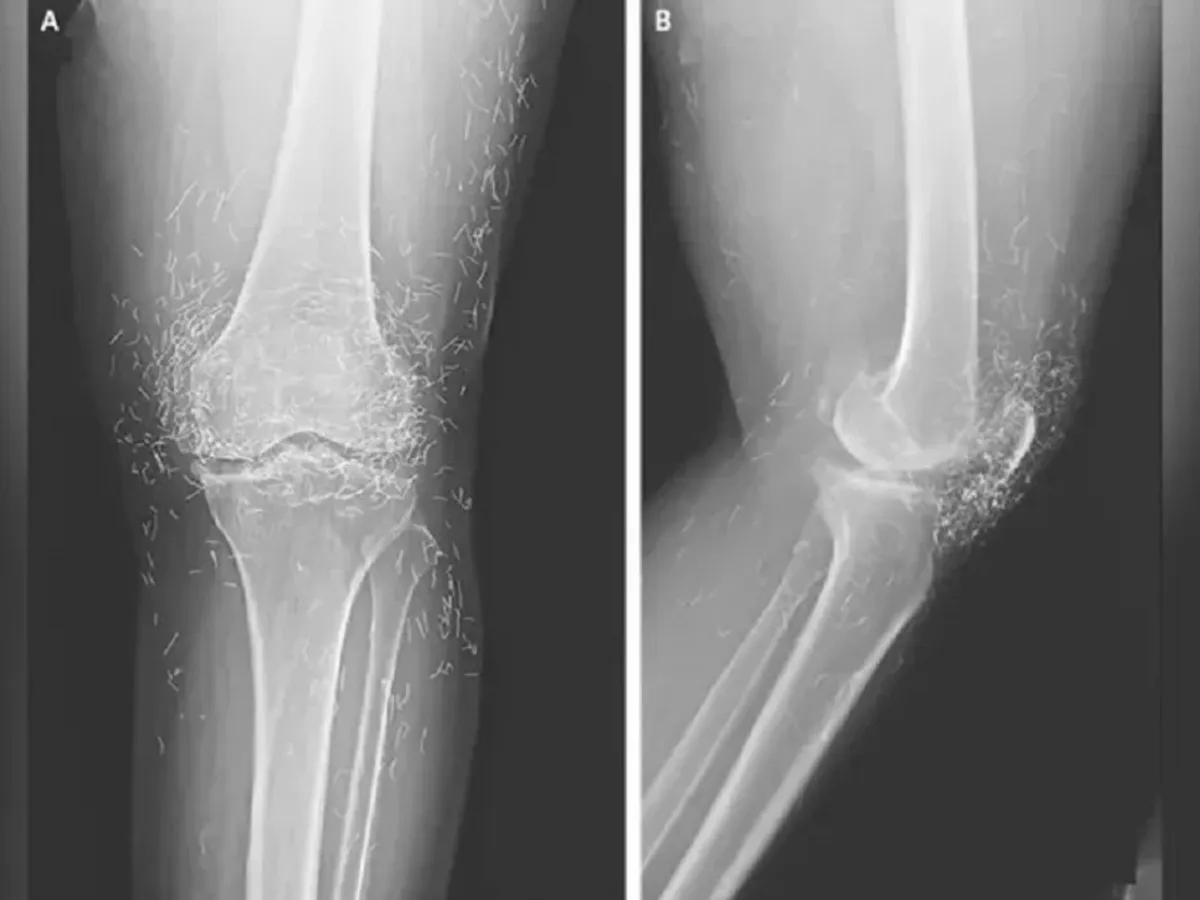

Radiografia genunchilor pacientei a arătat sute de fire de aur aflate în ei - Foto: The New England Journal of Medicine

O radiografie a relevat o îngroșare și o întărire a părții interne a tibiei, excrescențe osoase în genunchi - toate simptome comune ale osteoartritei - dar și sute de fire minuscule de aur încorporate în țesutul din jurul genunchiului, scrie odditycentral.com.